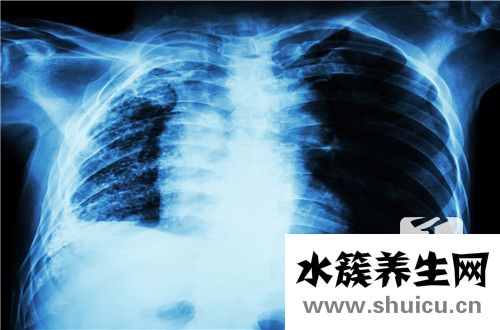

實(shí)際上,肺紋理便是做胸部影象查驗(yàn)時(shí)觀查到的放射性條形黑影,一切正常而言,這種黑影是由肺動(dòng)脈、肺靜脈、支氣管炎及淋巴血管構(gòu)成的,所以說一定總數(shù)的紋路是一切正常的,可是假如觀查到放射形黑影增加,基本就可以診斷為幾下肺紋理增多,建議立即明確病癥特性,盡快接納醫(yī)治。

一般來講,造成幾下肺紋理增多的原因有很多,有可能是生理性的一切正常狀況,也是有可能是生理性的,可是假如病人僅僅查驗(yàn)出肺紋理增多,病人本身卻沒有什么不適感反映,一般是沒什么很大影響的,不具備很大的臨床表現(xiàn),假如病人有難受的覺得,就一定要做更詳盡的查驗(yàn)。

據(jù)統(tǒng)計(jì),幾下肺紋理增多病人大多數(shù)是抽煙群體,因此 抽煙是很有可能造成肺紋理增多的,一樣,長(zhǎng)期處在環(huán)境污染、接納二手煙的群體也是會(huì)出現(xiàn)肺紋理增多的狀況的,因而在生活起居中,一定要搞好肺紋理增多的防范措施,例如在氣體混濁的地區(qū)佩戴口罩,霧霾天氣 氣溫還要帶口罩交通出行。

因此 ,幾下肺紋理增多實(shí)際上便是身體在吸進(jìn)了不干凈的氣體后,在肺臟產(chǎn)生的放射性條形黑影,一切正常的肺紋理是由肺動(dòng)脈、肺靜脈產(chǎn)生的,具備一定的總數(shù),一旦增加還是需要給與一定的高度重視的,觀查病人有沒有不適感,要是沒有得話基本是沒什么大問題的,如果有不適一定要立即到醫(yī)院門診接納醫(yī)治。